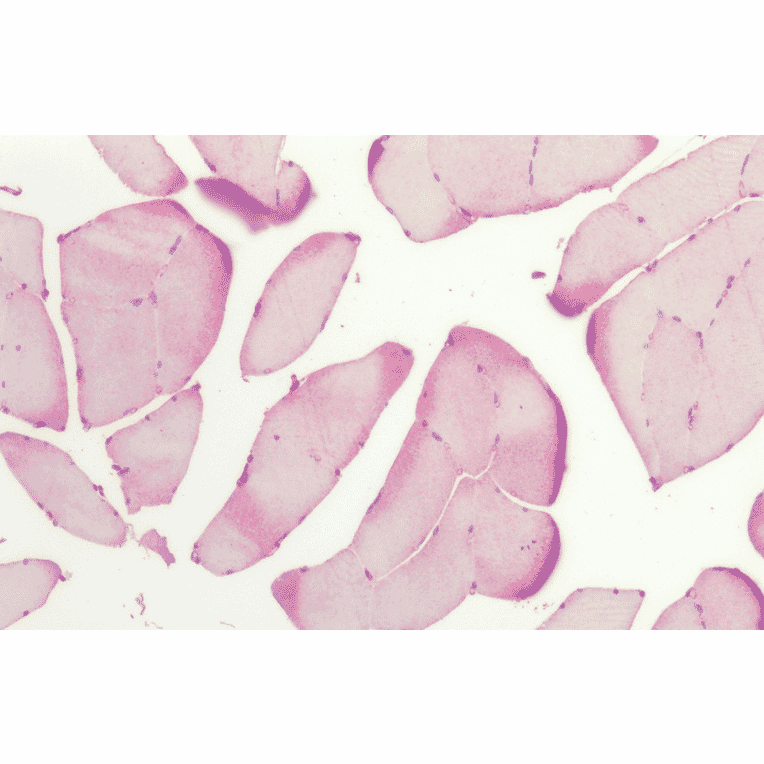

Immunohistochemistry analysis of human skeletal muscle, fixed in formalin and paraffin-embedded. The Primary Antibody used was Anti-HSP27 Antibody (A305135).